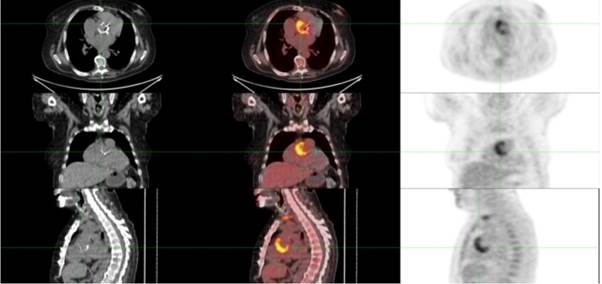

Con el planteo de EI probable, por criterios menores, sobre válvula protésica aórtica precoz, se inició tratamiento antibiótico, combinado y prolongado, con ampicilina, cefazolina y gentamicina. El diagnóstico se confirma mediante PET-SCAN (figura 4).

En este caso, el ETT y ETE inicial así como también el realizado al séptimo día fueron negativos. Frente a la alta sospecha clínica de EI, a pesar de no ser portador de prótesis mecánica, se solicitó un PET-CT que finalmente confirma la EI.

Las nuevas técnicas de imagen para el diagnóstico de EI se añadieron especialmente para casos con ETT o ETE negativos o no concluyentes. 3